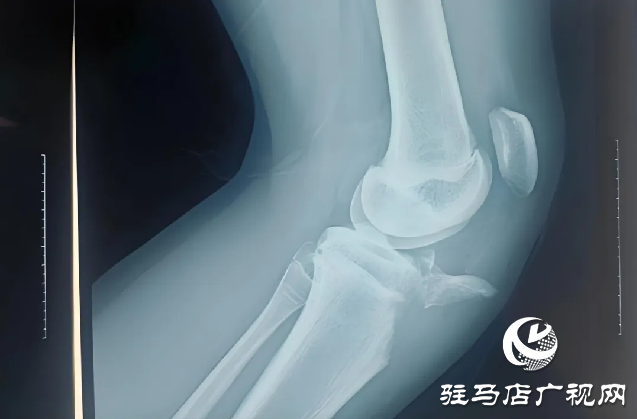

近日,胡同学在学校上楼梯时不慎摔倒,伤后感到左膝疼痛不适,活动不能,家人紧急送他来驻马店市第一人民医院骨科二病区。入院后完善相关检查,任耀医生根据胡同学的病情、影像学、术前检查,做出诊断:左胫骨结节撕脱性骨折;左髌韧带断裂。

驻马店市第一人民医院任耀医生提醒,胫骨结节撕脱骨折属运动损伤,较少见,好发于12-17岁男性青少年。损伤机制为股四头收缩(向心,离心)牵拉致伤,常见于加速跑,起跳,落地等发力瞬间,根据X线片骨折线走行及移位情况分为3型。临床表现为疼痛,主动伸膝行走、负重不能,X线可见胫骨结节骨折,髌骨上移,有时可合并髌腱断裂。

胫骨结节撕脱骨折的治疗方式主要分为两种:对于未发生移位的I型或Ⅱ型胫骨结节骨折,可以采取手法复位,膝关节伸直位石膏或支具固定;对于发生移位的Ⅱ型或累及关节面的III型骨折,应该积极进行手术治疗,多采取切开复位内固定,内固定材料选择空心钉或克氏针固定为主,避免损伤骨骺生长板。